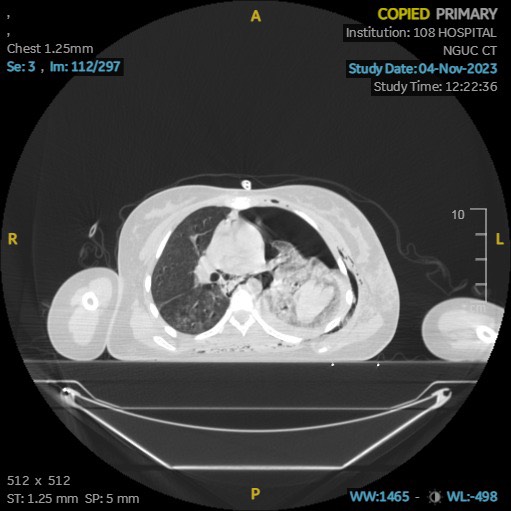

Sau thăm khám, bác sĩ chẩn đoán sơ bộ: Chấn thương ngực kín do tai nạn giao thông dập phổi trái, gãy 5 xương sườn, tràn khí màng phổi trái mức độ nhiều. Bệnh nhân được đặt dẫn lưu màng phổi trái, ra rất nhiều khí. Sau khi đặt dẫn lưu, tình trạng hô hấp bệnh nhân không cải thiện, dẫn lưu vẫn ra khí liên tục. Trên chụp CT ngực kiểm tra thấy phổi trái vẫn xẹp, có ổ tụ máu trong phổi ở thùy dưới.

Phim chụp CT cho thấy tổn thương phức tạp của bệnh nhân. ảnh: BVCC